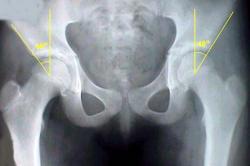

Шеечно-диафизарным углом (инклинация шейки бедра) называют угол пересечения продольной оси диафиза с осью шейки бедра. Существуют возрастные половые и индивидуальные различия в величине нормального шеечно-диафизарного угла. В младенческом. и раннем детском возрасте он больше, чем у взрослых, у взрослых больше, чем у престарелых. Возрастные колебания угла составляют 20-25° (144° у маленьких детей, 120° у стариков). В среднем нормальный шеечно-диафизарный угол равен у взрослых 126-130°.

Если шеечно-диафизарный угол меньше среднего угла, соответствующего возрасту, то такое состояние называют варусной деформацией шейки - соха vara, если он более среднего угла - вальгусной деформацией - соха valga. Уменьшение инклинации шейки бедра может быть врожденным (соха vara congenita) и приобретенным (соха vara acquisita).